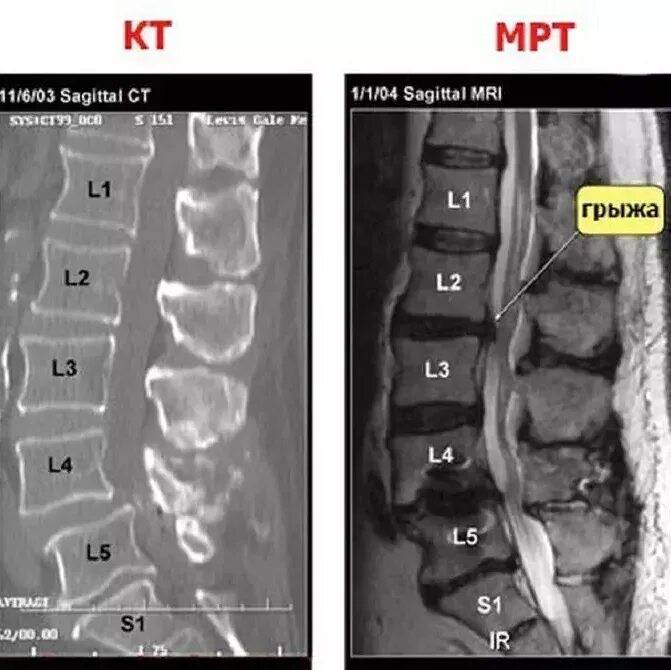

Что более информативно кт или мрт